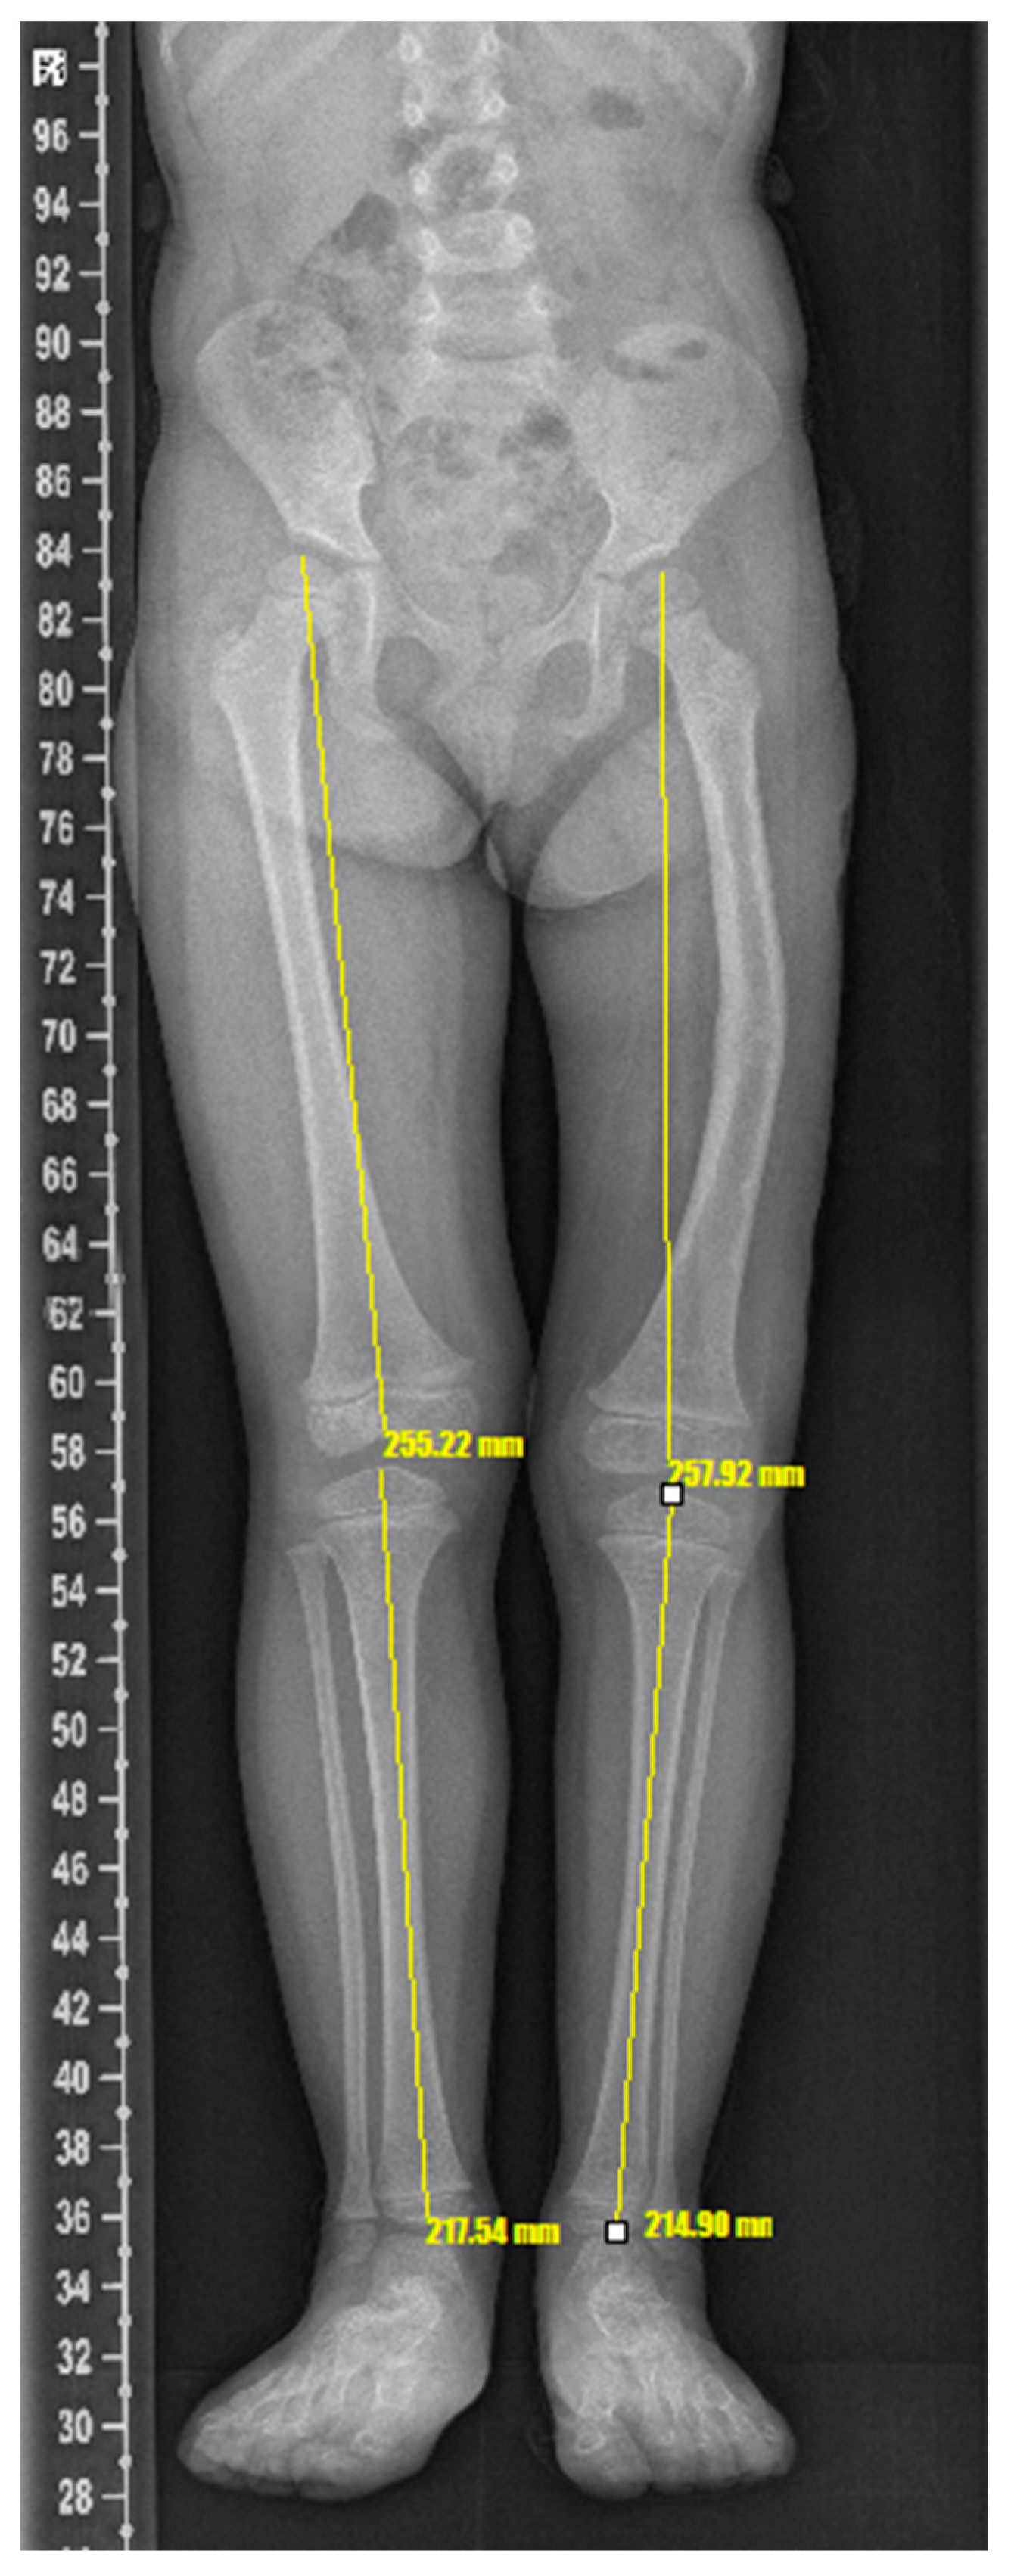

2. Case Description